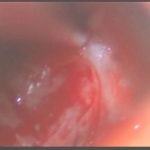

術中写真

摘出 前